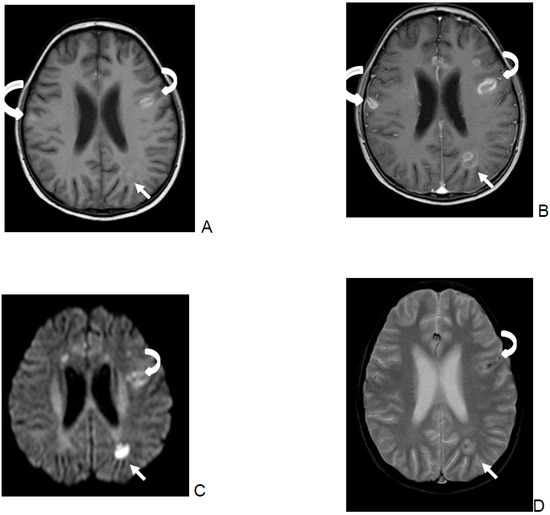

- SWI/T2* were evaluated as follows:

- Parenchymal bleeding was defined as a hypointense parenchymal signal with “blooming”.

- Cluster of microbleeding was defined as a significantly hypointense cluster signal.

- Perivascular microbleeding was defined as a significantly hypointense perivascular signal.

- Ring-like was defined as a hypointense ring-like signal.

- Vascular blooming was defined as a vascular structure with signal loss and prominent “blooming” on SWI/T2*w sequences.

| Outcome | Parenchymal Bleeding | Cluster of Microbleeds | Perivascular Microbleeding | Rim-Like | Vascular Blooming |

|---|---|---|---|---|---|

| Total number of patients | 5 | 4 | 3 | 9 | 2 |

| Died | 2 | 1 | 2 | 4 | 1 |

| Severe neurological sequelae | 0 | 2 | 1 | 2 | 0 |

| Favorable outcome | 3 | 1 | 0 | 3 | 1 |